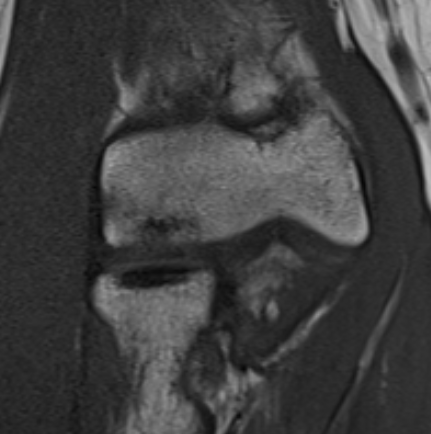

MRI

Fluid interface denotes detachment / instability

MRI Classification

Stable

- cartilage intact

- no fluid behind lesion

Unstable

- cartilage breach

- fluid behind lesion